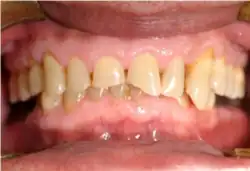

Mouth

Acid reflux into the mouth can cause breakdown of the enamel, especially on the inside surface of the teeth. A dry mouth, acid or burning sensation in the mouth, bad breath and redness of the palate may occur.[27] Less common symptoms of GERD include difficulty in swallowing, water brash, chronic cough, hoarse voice, nausea and vomiting.[26]

Signs of enamel erosion are the appearance of a smooth, silky-glazed, sometimes dull, enamel surface with the absence of perikymata, together with intact enamel along the gum margin.[28] It will be evident in people with restorations as tooth structure typically dissolves much faster than the restorative material, causing it to seem as if it "stands above" the surrounding tooth structure.[29]